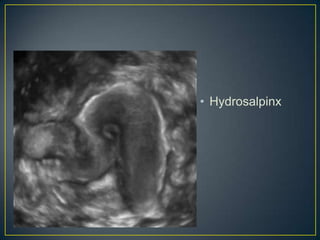

• Fusiform anechoic

structure

• Tapers towards the

uterus

• No peristalsis

• Hydrosalpinx